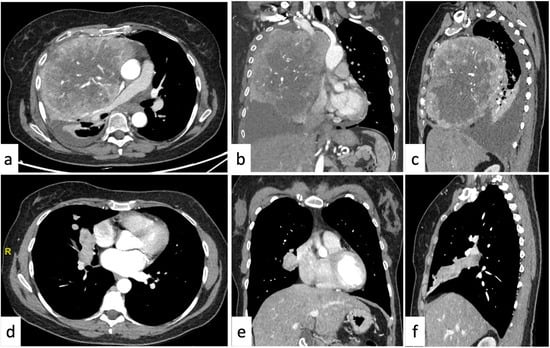

2.4. More than One Mediastinal Compartment

| >1 compartment (11.2%) | Liposarcoma Lipomatosis | Lymphangioma | Lymphadenopathy Lung cancer |

3.1. Pleural Neoplasms

- Sureka, B.; Thukral, B.B.; Mittal, M.K.; Mittal, A.; Sinha, M. Radiological Review of Pleural Tumors. Indian J. Radiol. Imaging 2013, 23, 313–320. [Google Scholar] [CrossRef]

- Bonomo, L.; Feragalli, B.; Sacco, R.; Merlino, B.; Storto, M.L. Malignant Pleural Disease. Eur. J. Radiol. 2000, 34, 98–118. [Google Scholar] [CrossRef] [PubMed]

- Bibby, A.C.; Tsim, S.; Kanellakis, N.; Ball, H.; Talbot, D.C.; Blyth, K.G.; Maskell, N.A.; Psallidas, I. Malignant Pleural Mesothelioma: An Update on Investigation, Diagnosis and Treatment. Eur. Respir. Rev. 2016, 25, 472–486. [Google Scholar] [CrossRef]

- Luerken, L.; Thurn, P.L.; Zeman, F.; Stroszczynski, C.; Hamer, O.W. Conspicuity of Malignant Pleural Mesothelioma in Contrast Enhanced MDCT—Arterial Phase or Late Phase? BMC Cancer 2021, 21, 1144. [Google Scholar] [CrossRef]

- Nickell, L.T.; Lichtenberger, J.P.; Khorashadi, L.; Abbott, G.F.; Carter, B.W. Multimodality Imaging for Characterization, Classification, and Staging of Malignant Pleural Mesothelioma. Radiographics 2014, 34, 1692–1706. [Google Scholar] [CrossRef]